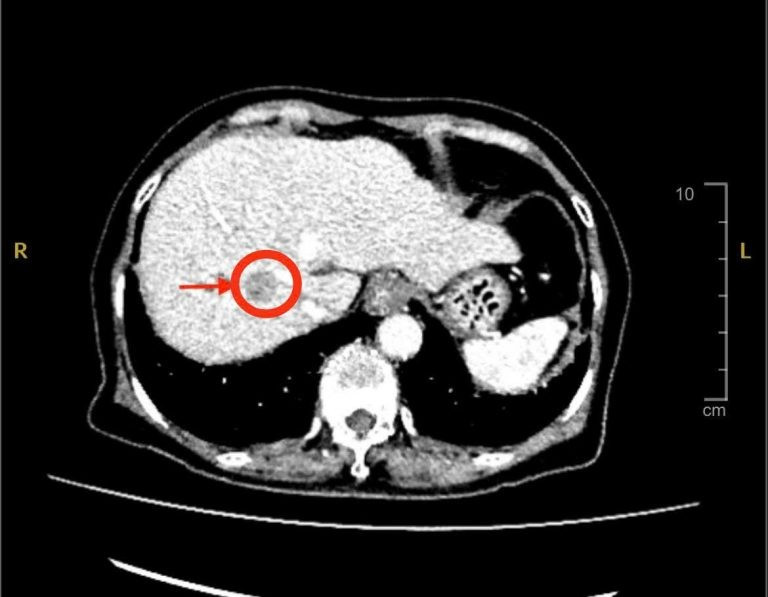

Với tiền sử bệnh xơ gan đang theo dõi và điều trị, xơ gan lại là yếu tố nguy cơ cao của ung thư gan, các bác sĩ nghi ngờ đây có thể là dấu hiệu đầu tiên của bệnh. Vì thế, bác sĩ chỉ định cho bệnh nhân siêu âm bụng và chụp MSCT thì phát hiện có khối u gan bên phải với kích thước khoảng 2cm, nghĩ nhiều đến ung thư nguyên phát tế bào gan (HCC) – một dạng ung thư gan phổ biến ở người có bệnh nền xơ gan, viêm gan B hoặc viêm gan C.

Hình ảnh CT khối u gan - Ảnh BVCC

Sau khi xem xét kỹ kết quả, các bác sĩ đánh giá khối u còn trong giai đoạn có thể điều trị triệt căn, lựa chọn đốt khối u lại không khả thi do khối u nằm sâu trong nhu mô và sát mạch máu lớn nên việc cắt gan phải được đưa ra. Song song với việc phải đảm bảo thể tích gan trái còn lại đủ duy trì chức năng và đảm bảo rìa diện cắt triệt căn ung thư cũng như ngăn ngừa tái phát.